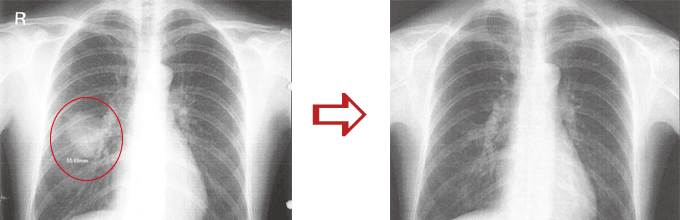

肺癌、手術後

横内漢方治療前と後